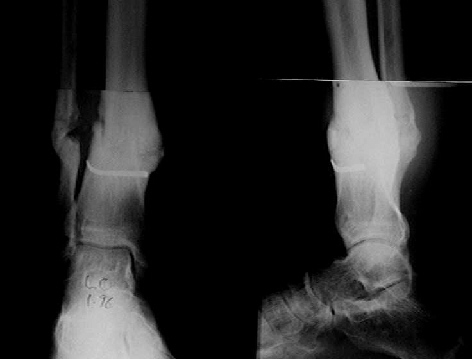

The situation at the ankle is now like a stiff non-union.

The cartilages destroyed by the infection, there is only bone proximal (tibia) and bone distal (talus)

Putting this under distraction would very likely lead to a consolidation of the 'gap' created with bone.

This supports Alex's proposal for closed distraction.

In one of my cases, with a non-union of the distal tibia, and a stiff ankle with equinus, as part of the treatment, I distracted the ankle, with the hope of 'loosening' up the ankle, and correcting the equinus,

To my surprise, this distracted area made bone, effectively converting a painful, stiff, fibrous ankle into a solidly fused, painless ankle.

Pic attached - the transarticular K wire/steinman pin was put in by the previous surgeon, to stabilise what was apparently a very unstable

ankle.

I don't have his pre-distraction pics, but take my word for it, the ankle space was seen, though hazy, and the patient had pain on attempted movts of the ankle.

Mangal Parihar